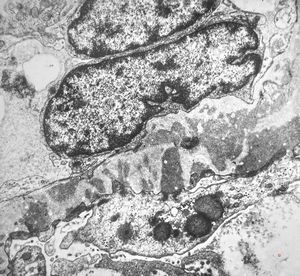

M,58y. | membranous glomerulopathy -early stage

F,26y. | membranous glomerulopathy